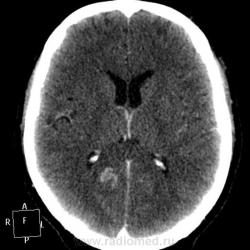

Мужчине 67 лет. У меня нет четкого мнения об изменении в правой затылочной доле. Ваше мнение?

"Непонятная штука в затылочной доле"-вероятнее артерио-венозная мальформация.Гиподенсная зона,прилежащая к ней-отдаленное последствие кровоизлиния из АВМ.

Может кавернома.

Склоняюсь к АВМ, прослеживается приводящий и отводящий сосуды. Не совсем понятно понижение плотности между сосудистыми петлями (может, коллега gar70 прав/а). Рекомендовала МРТ после выписки из сосудистого отделения (у нас такие вещи, что бы из сосудистых аномалий ни было, не оперируют).